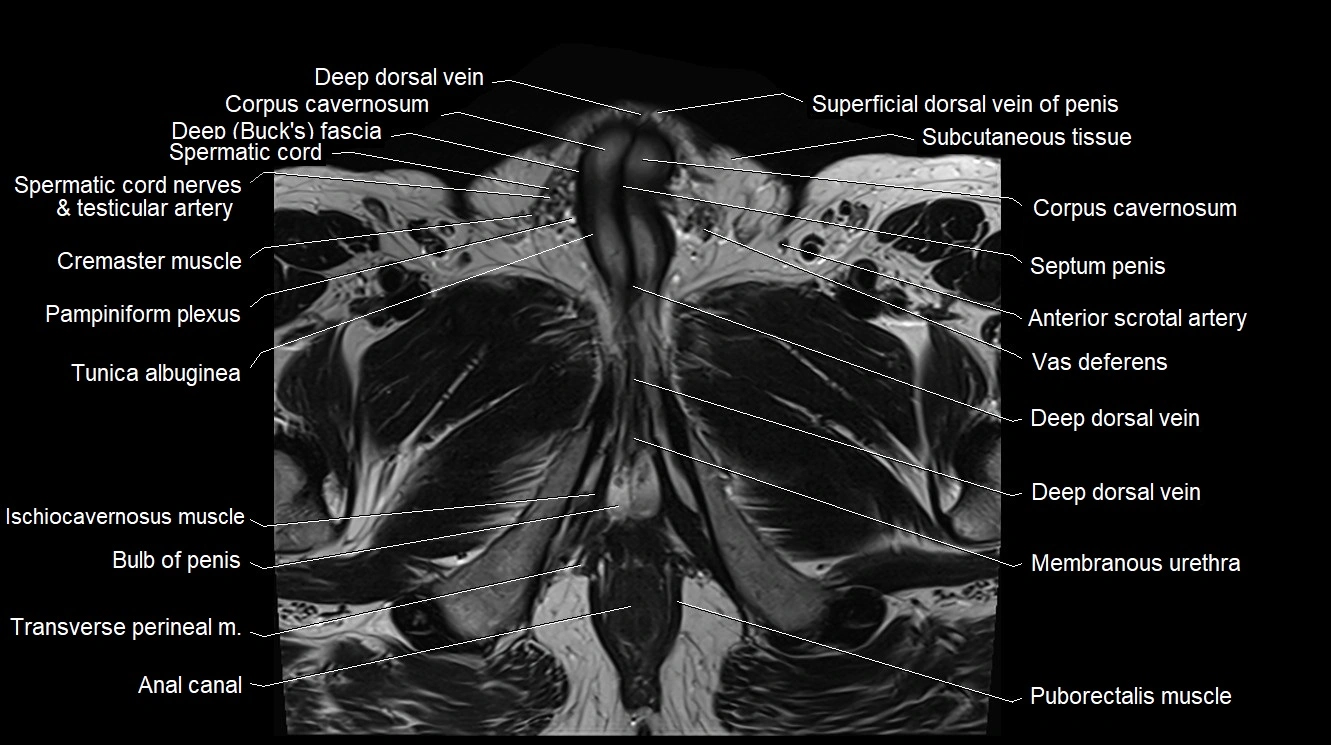

- Anal canal

- Bulb of Penis

- Bulbospongiosus muscle (Male)

- Corpus cavernosum

- Cremaster muscle

- Crus of penis

- Deep dorsal vein of the penis

- Deep transverse perineal muscle

- Ischiocavernosus muscle (Male)

- Membranous urethra

- Pampiniform plexus

- Puborectalis muscle

- Septum of the penis (Penile septum)

- Spermatic cord

- Spermatic cord nerves

- Superficial dorsal vein of penis

- Transverse perineal muscle

- Tunica albuginea (penis)

- Vas deferens